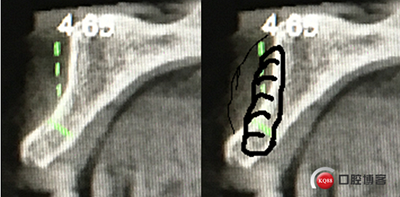

“以修復(fù)為導(dǎo)向”,在前牙種植體中心點就是未來牙冠舌側(cè)窩位置。那這個病例植體的方向和位置就只能是下圖右側(cè)這樣了。很明顯植體根尖部分要穿出唇側(cè)倒凹的。怎么辦?翻大瓣植骨蓋膜減張縫合?不!可以不翻瓣,大家仔細看看下圖右圖我畫的那條細細的弧線,是不是跟原來唇側(cè)凹陷的骨面成為左右對稱的兩條弧,也就是說骨膜從原來唇側(cè)凹陷骨面上剝離然后放到左側(cè)我畫的那條弧線那里根本不需要減張,這兩條弧線之間也就是唇側(cè)凹陷處放上骨粉,骨膜不會增加張力。不知道大家看明白了沒有。